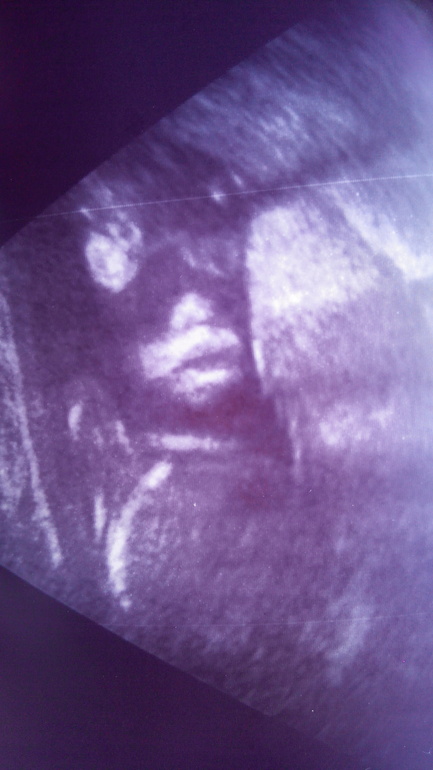

Урррра! Сходила! Видела!😄 😂

Все у нас хорошо! Параметры, как в таблице- тютилька в тютельку. 😍Отвечаем возрасту 21,2. Вес 407 гр. ЧСС 129. Обвития нет☺😘🙌

У меня второй сыночек! Я безумно рада! Муж, дочу хотел, а я сынулю. Но сказал, что рад. Два сына.😘😍🙌

Фото дали, причендалы показали, сказала врач, что у нас хозяйство боооольшое, или писать хочет😹